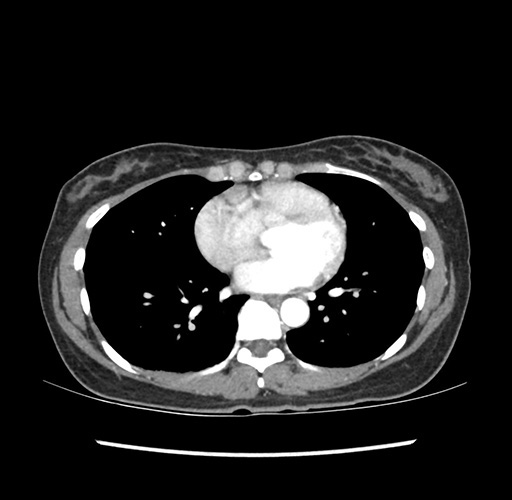

Imaging Analysis

Look through the patient's CT scan to identify any areas of concern for the necessary procedure.

Based on your CT findings, which issue(s) would give reason for "planned slowing down moment(s)" in this case?

Considering a standard left lateral sectionectomy procedure, what step(s) of the operation would you do differently in this case ?